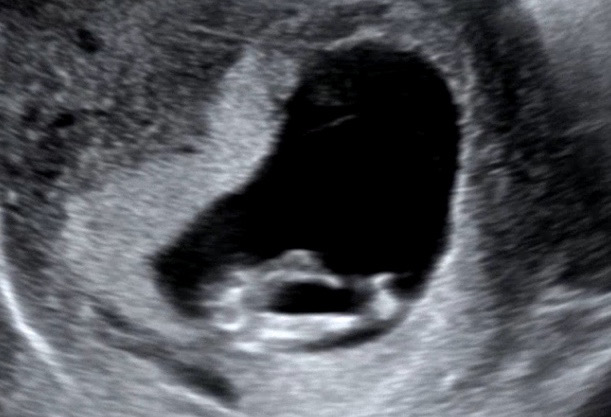

11주 다리사이 초음파

어때보이세요?

딸일거같아요~ ㅋㅋ저는 존재감이 확실히 있더라구요